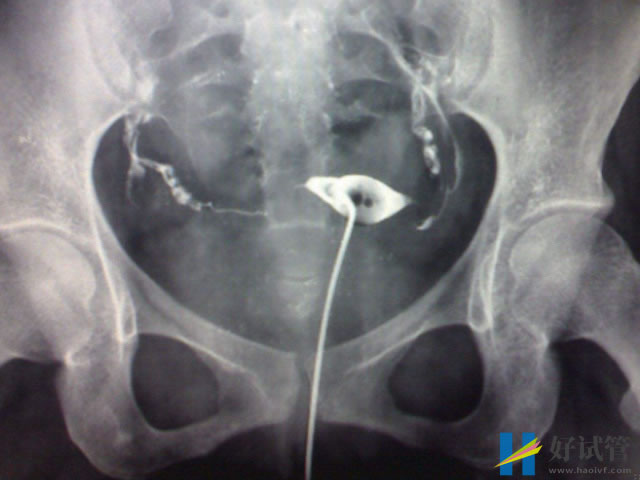

- 输卵管闭塞不通:大概率是因为结核、附件炎、宫外孕、输卵管结扎等因素导致的,一般通过腹腔镜或宫腔镜检查可以直观的判断,可以采用西医以导丝复通术为主进行治疗;